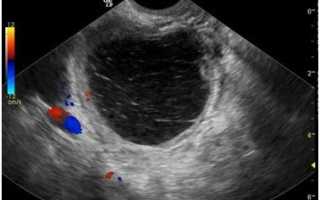

Так выглядит гиперэхогенное образование на экране УЗИ

Основным методом диагностики является ультразвуковое исследование (УЗИ) органов малого таза. УЗИ позволяет визуализировать матку и выявить наличие гиперэхогенных образований. Гиперэхогенные участки на УЗИ выглядят как светлые области, что указывает на их плотность и состав. Важно отметить, что гиперэхогенные образования могут быть как доброкачественными, так и злокачественными, поэтому дальнейшее обследование необходимо для уточнения диагноза.